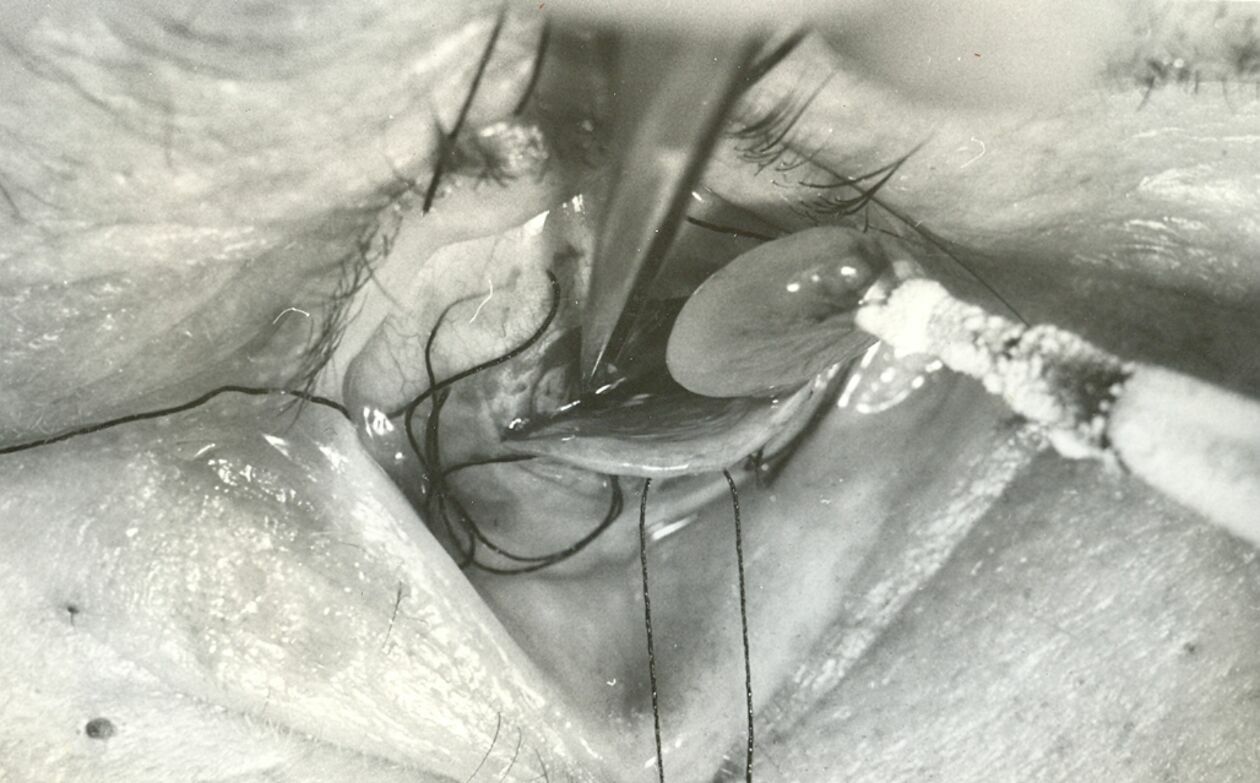

Wszystko rozpoczęło się od profesora Tadeusza Krwawicza, który w latach 1948-1980 był kierownikiem Katedry i Okulistyki lubelskiej Akademii Medycznej(dziś Uniwersytet Medyczny). Zapoczątkował on uniwersyteckie nauczanie okulistyki i to dzięki niemu powstał pierwszy ośrodek w Lublinie, leczący ludzi w tym zakresie. Prof. Krwawicz nadał od razu wysoki poziom działań badawczych i klinicznych. Słynny okulista z Lublina opracował nowe metody, dzięki którym leczył zaćmę, co zdecydowanie było zaskoczeniem w środowisku lekarskim i zostało uznane na arenie międzynarodowej. Wprowadził on do okulistyki krioterapię, która zakładała, że przy obniżonej temperaturze, leczenie oczu, głównie usuwanie zmętniałej soczewki staje się prostsze i skuteczniejsze. Dało to szansę wielu osobom ze ślepotą, aby mogły znów normalnie widzieć.

- W tej chwili nie są kontynuowane te pierwsze metody wprowadzone przez prof. Krwawicza, ale w dalszym ciągu rozwijane są jego idee. On był pionierem w usuwaniu zaćmy. Krioterapię w chirurgii z pewnymi modyfikacjami używa się do dziś. Teraz są jednak inne narzędzia i sprzęty, ale jego idea wciąż jest żywa. Dlatego właśnie prof. Krwawicz został nagrodzony przez Amerykańską Akademię Okulistyki włączeniem, do tzw. „hall of fame” światowej okulistyki. To bardzo renomowana akademia, co oznacza, że metody i idee, które zostały opracowane w Lublinie, zostały dzięki profesorowi docenione na całym świecie –mówi prof. dr hab. n. med. Robert Rejdak, kierownik Kliniki Okulistyki Ogólnej i Dziecięcej UM w Lublinie, prorektor ds. umiędzynarodowienia i cyfryzacji UM w Lublinie.

Fakoemulsyfikacja soczewki polega na rozbijaniu zmian chorobowych za pomocą ultradźwięków, usuwanie soczewki i wymiana na nową. Witrektomia natomiast polega na wycięciu zmienionego chorobowo ciała szklistego z gałki ocznej.